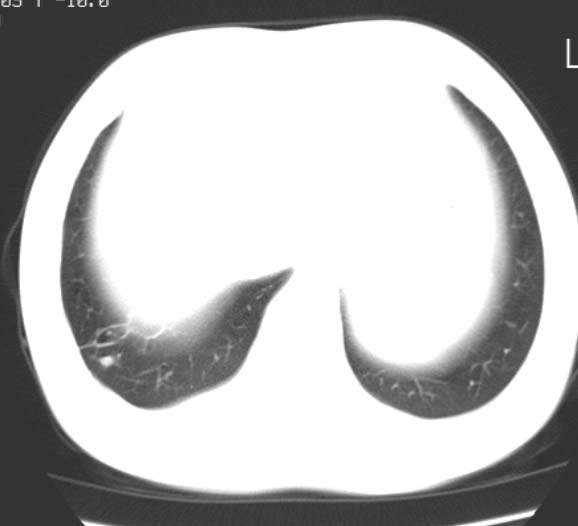

标题: CT25816:胸部CT,请会诊。

女 19岁,发热,咳嗽

病人是一个留守女孩儿,在医院抗炎治疗了两天,不发热就出院了,连确诊的机会都没有!